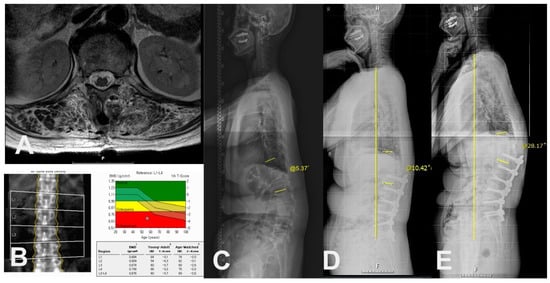

| Muscular quantity of T12-L1 (CSA of erector spinae), cm2 | 23.8 ± 4.2 | 32.2 ± 10.1 | <0.001 * |

| Muscular quality of T12-L1 (Fat infiltration in CSA of erector spinae) | <0.001 * | ||

| Mild to moderate (<50%), n | 4 | 21 | |

| Severe (≥50%), n | 13 | 3 | |

| BMD (T-score) | −2.4 ± 0.8 | −1.5 ± 1.1 | 0.006 * |

| Osteoporosis, n (%) | 14 (60.9) | 4 (12.1) | <0.001 * |